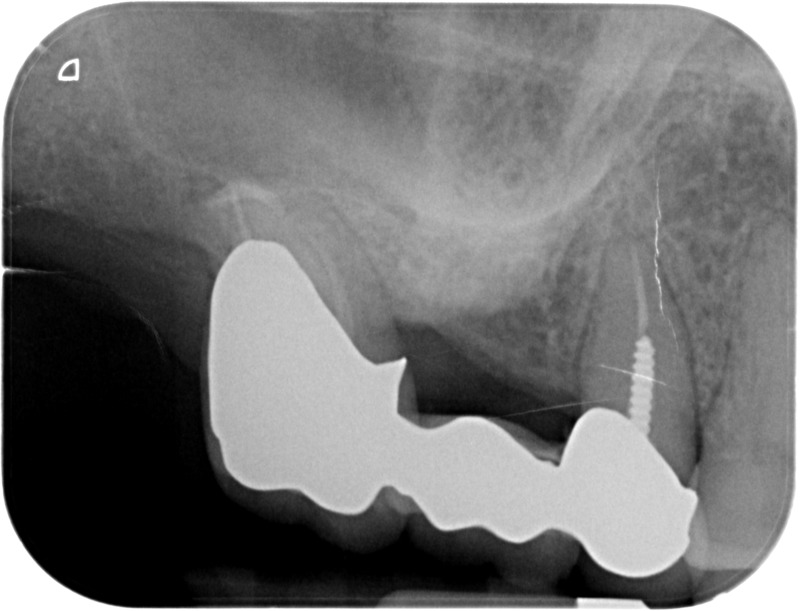

• Traitement endodontique : Sous anesthésie locale et à travers la protection d’un champ opératoire nous accédons à la pulpe de la dent à soigner, puis aux canaux de ses racines que nous devons désinfecter. Ce soin nécessite l’élimination complète de la source de contamination (souvent la carie) parfois sous une ancienne reconstitution ou une couronne qu’il faut alors retirer. Une fois le nettoyage et la mise en forme des canaux réalisés, nous les obturons de façon hermétique avec un ciment et un matériau thermoplastique appelé Gutta Percha. Ceci afin d’empêcher une nouvelle prolifération bactérienne et d’assurer le maintien de la dent dans ses structures de soutien (ligament parodontal et os alvéolaire). L’ouverture effectuée au centre de la dent sera d’abord refermée avec un pansement provisoire avant d’envisager ensemble la reconstitution d’usage : un composite, un inlay-onlay ou une couronne.

Avant